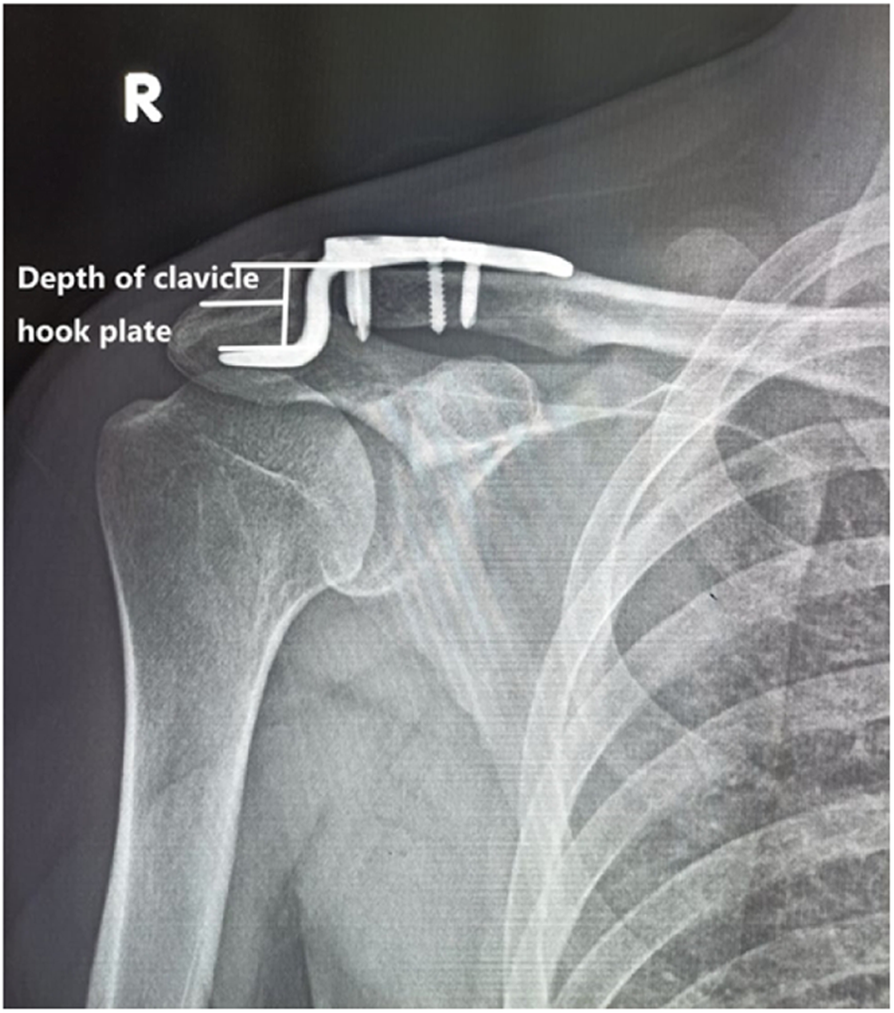

Fig. 3From: To explore the reasonable selection of clavicular hook plate to reduce the occurrence of subacromial impingement syndrome after operationThe depth of the hook plate used in the patientBack to article page